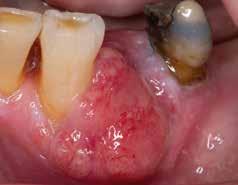

Das Tumorboard empfahl eine chirurgische Tumorresektion, seitliche Halsdissektion (links) und die Deckung mit einem Zungenlappen (Abb. 6). Ein Teil des Alveolarfortsatzes mit dem Tumor inklusive dreier Zähne (31, 32, 33) wurde reseziert. Makroskopisch zeigte sich ein maximal 1 cm breiter bis an das Periost reichender Tumor, ohne Infiltration des Kieferknochens. Insgesamt sechs resezierte regionale Lymphknoten zeigten reguläre Architektur. Mikroskopisch zeigte sich ein eindeutiger Übergang des regulären Epithels mit Formationen eines invasiv wachsenden, malignen epithelialen Tumorgewebes mit nestund strangartiger Architektur. Der Tumor zeigte eine maximale Ausdehnung von 2,2 cm bei einer Tiefenausdehnung von 1 cm.

Abb. 6: Intraorale Ansicht Unterkiefer nach Tumorresektion, Deckung mit Zungenlappen und nach Beschliff